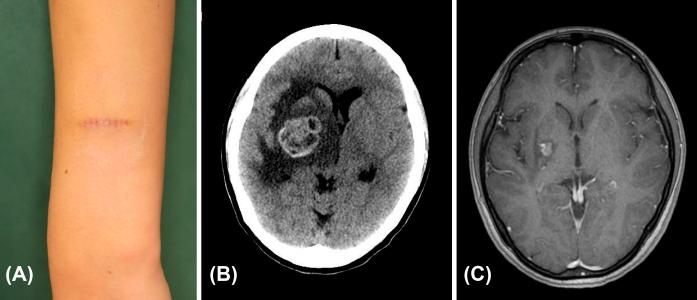

Brain metastases from malignant tumors are generally known to have a poor prognosis. One of the major reasons for this is the lack of efficacy of anti-tumor drugs compared to other organs. One of the major reasons for this is the lack of efficacy of anti-tumor drugs compared to other organs. Malignant melanoma is a highly malignant tumor that occurs mainly in the skin and is relatively prone to brain metastasis. In this case report, we report two cases of malignant melanoma with brain metastases that were treated with a combination of radiotherapy and chemotherapy and had long-term survival. Case 1 was a 51-year-old Japanese man with primary melanoma of the chest; the pathological staging was pT4aN1aM0, stage IIIC. He developed multiple brain metastases two years and three months after the initial resection. Case 2 was a 23-year-old Japanese woman with primary melanoma of the upper extremities; the pathological staging was pT1bN1aM0, stage IIIA. She developed brain metastases one year and nine months after the initial resection. Both patients had positive BRAF gene mutations in their primary tumors. The combination of BRAF inhibitors, immune checkpoint inhibitors, and stereotactic radiotherapy resulted in long-term survival of more than 5 years for Case 1 and more than 6 years for Case 2. With advances in chemotherapy and radiotherapy, the prognosis for patients with brain metastases, not only malignant melanoma, is expected to improve further in the future. Although rare, malignant melanoma is known to occur in various organs other than the skin. We report this case because we believe that our case report will be of interest to physicians who treat the above organs.

恶性肿瘤的脑转移通常预后较差。其中一个主要原因是与其他器官相比,抗肿瘤药物的疗效欠佳。恶性黑色素瘤是一种高度恶性的肿瘤,主要发生于皮肤,相对容易发生脑转移。在本病例报告中,我们报告了两例脑转移恶性黑色素瘤患者,他们接受了放疗和化疗联合治疗并长期存活。病例1是一名51岁的日本男性,患有胸部原发性黑色素瘤;病理分期为pT4aN1aM0,IIIC期。在初次切除术后两年零三个月,他出现了多发脑转移。病例2是一名23岁的日本女性,患有上肢原发性黑色素瘤;病理分期为pT1bN1aM0,IIIA期。在初次切除术后一年零九个月,她出现了脑转移。两名患者的原发性肿瘤中BRAF基因均呈阳性突变。BRAF抑制剂、免疫检查点抑制剂和立体定向放疗联合应用使病例1存活超过5年,病例2存活超过6年。随着化疗和放疗技术的进步,未来不仅是恶性黑色素瘤脑转移患者,其他脑转移患者的预后有望进一步改善。恶性黑色素瘤虽然罕见,但已知可发生于皮肤以外的各种器官。我们报告此病例是因为我们相信我们的病例报告将引起治疗上述器官疾病的医生的兴趣。